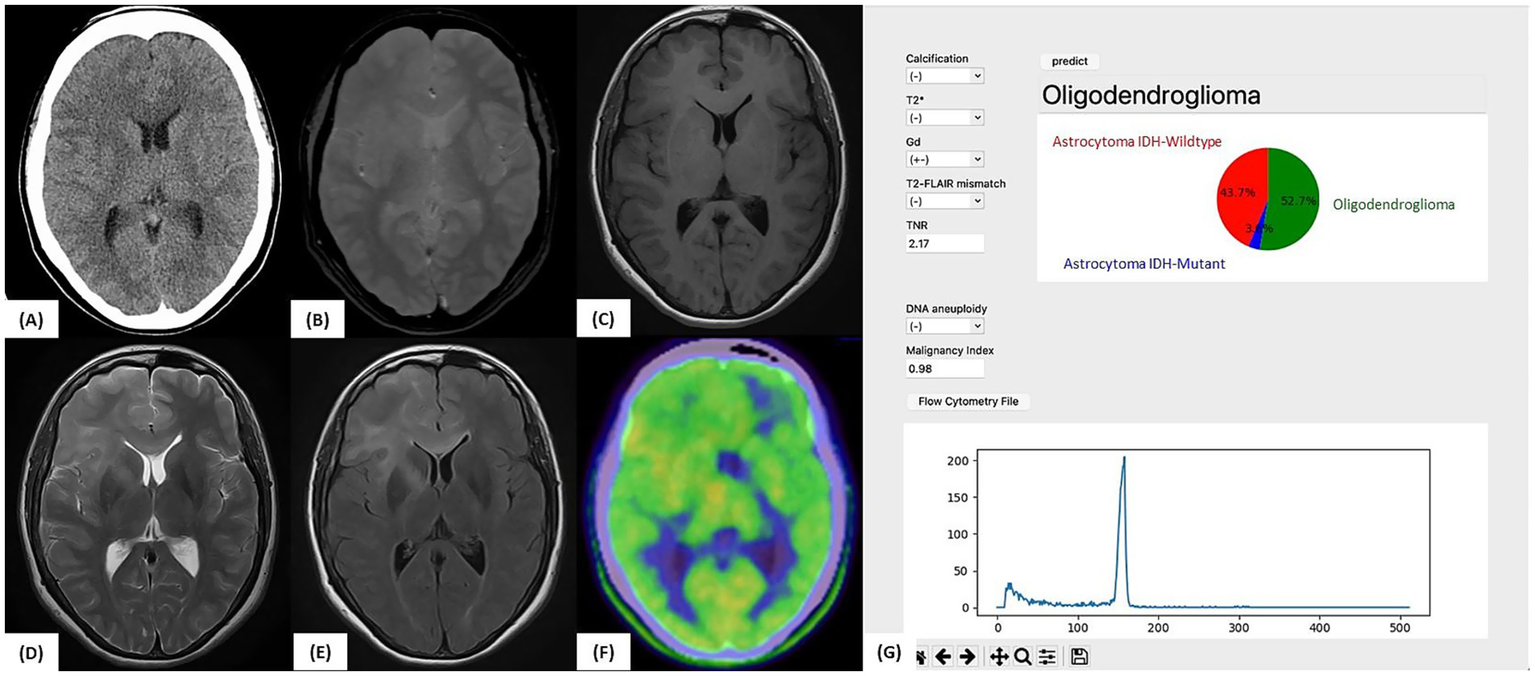

3.4.2 Illustrative case 2

A 32-year-old woman underwent MRI for headache, which revealed a diffuse FLAIR hyperintense lesion extending from the right frontal lobe to the left frontal lobe via the corpus callosum, raising suspicion of gliomatosis cerebri (Figure 6). No apparent calcification, T2-FLAIR mismatch, or contrast enhancement was observed. Initial Met-PET showed mild uptake (TNR = 1.54).

Figure 6

Illustrative case 2: Artificial intelligence prediction exceeding preoperative expectations. (A) Preoperative CT and (B) T2*-weighted MRI showing no evidence of calcification. (C) Gadolinium-enhanced T1-weighted MRI without any contrast enhancement. (D) T2-weighted MRI and (E) FLAIR image showing diffuse high-signal lesions without a T2-FLAIR mismatch. (F)11C-methionine PET showing mildly increased tracer uptake (tumor-to-normal uptake ratio = 2.17). (G) Intraoperative prediction result generated by the support tool. Based on preoperative imaging and intraoperative flow cytometry data (aneuploidy-negative, malignancy index = 0.98), the predicted molecular subtype was “Oligodendroglioma” (52.7%), followed by “Astrocytoma, IDH-wild-type” (43.7%). The final molecular diagnosis confirmed oligodendroglioma, WHO CNS grade 2, with an IDH1 mutation, 1p/19q co-deletion, and TERT promoter mutation, consistent with the intraoperative AI-based prediction.

After pregnancy, the lesion enlarged, prompting a stereotactic biopsy of the right frontal lobe and corpus callosum. A second Met-PET scan showed elevated uptake (TNR = 2.17) in the subcortical region of the right frontal lobe. Although Astro-WD was suspected based on imaging, iFC analysis revealed no aneuploidy and a low MI (0.98). The application predicted “Oligo: 52.7%, Astro-WD: 43.7%.”

Postoperative genetic testing confirmed the IDH1 R132H mutation, 1p/19q co-deletion, and pTERT mutation, resulting in a final diagnosis of oligodendroglioma, WHO CNS grade 2. This case demonstrates how artificial intelligence (AI)-assisted prediction provides accurate classification, even when clinical impressions differ, highlighting its value as an intraoperative support tool.